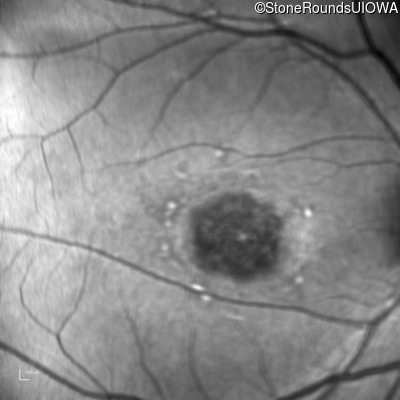

Infrared Fundus Photograph - Left - 20/100

Exemplar